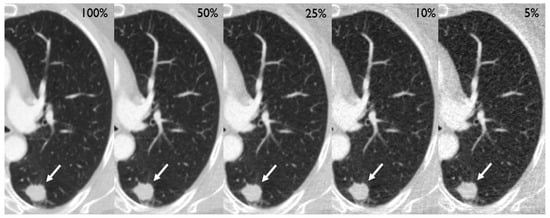

After preparation of the simulations, the CT scans of 210 patients (mean age [SD] 64.5 [9.2] years, 87 females [41%]) containing 250 tumors of the lung (201 solid, 28 part-solid, and 21 ground glass) could be included in the analysis (Table 1). Two exemplary cases are depicted in Figure 2 and Figure 3. Eight patients had to be excluded due to technical reasons, such as incomplete coverage of the lungs.

Figure 2.

Different dose level simulations depicting a 19 mm primary adenocarcinoma in the left lower lobe of a 71-year old female (white arrow), who had initially presented with a cough.